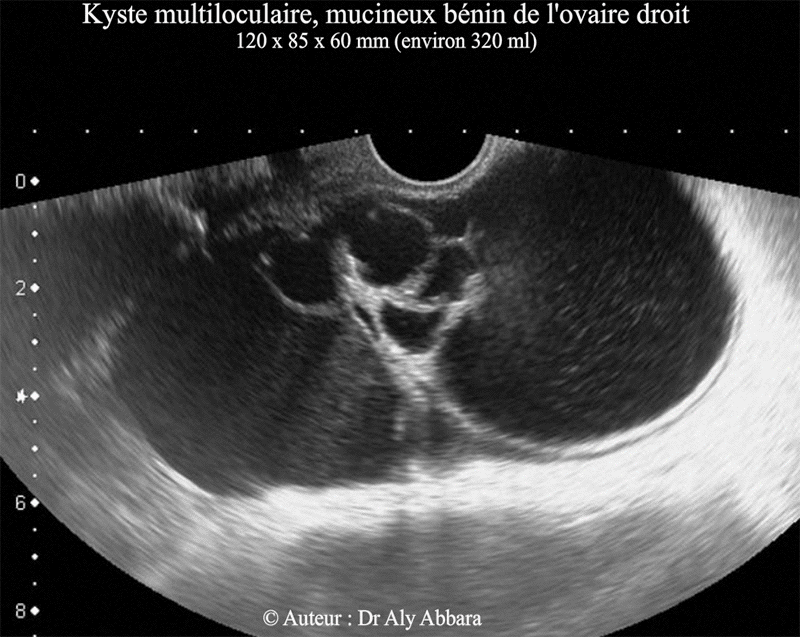

- Images échographiques d'un kyste mucineux pluriloculaire et bénin de l'ovaire droit avec son aspect macroscopique à titre de comparaison.

- Il s'agit d'un kyste multiloculaire de 120 x 85 x 60 mm de dimensions (soit environ 320 cm3 de volume).

L'examen anatomopathologique confirme sa nature mucineuse bénigne.

- Cette tumeur kystique de l'ovaire droit, a été découverte chez une patiente âgée de 63 ans, lors de l'examen clinique puis l'échographie

endovaginale, dans le cadre d'un bilan pour douleur abdomino-pelvienne aiguë.

- La laparotomie montre qu'il s'agit d'une tumeur kystique ovarienne droite compliquée d'une torsion non nécrosante.

- Tous les dosages des marqueurs tumoraux plasmatiques étaient normaux (CA 125, CA 19:9, antigène carcino-embryonnaire, hCG et alpha fœtoprotéine).